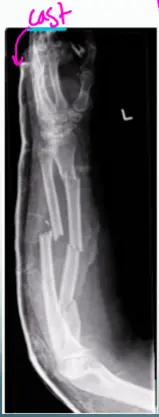

- x-ray AP and lateral view of forearm, show a displaced fracture in both radius and ulnar shaft with elbow dislocation

Extra Information

- cast, slab, splint, traction pin, implants

Cast

- X-ray AP view of Lt femur, fracture of distal femur with slab, Thomas splint

- X-ray AP view of Rt distal femur, presence of traction pin

- X-ray AP view of Lt femur, fracture in distal femur with plate and screws

Site â midâshaft forearm

Fracture type â simple radius & ulna

Fracture line â transverse across both bones

Displacement â 90° rotation of radius & ulna

Imaging â one joint captured in an AP view, the other in a lateral view on the same film

Special considerations â accurate anatomical reduction and absolute stability (a joint) are essential; note that TheddyâSlongo principles may not apply to forearm fractures.

Review the fracture lines carefully.

Site: midâshaft forearm

Type: simple radius / simple ulna fracture

Fracture line: transverse across both radius and ulna

Displacements:

- 90° rotation of both bones

- 35° posterior tilt of both bones

Special issues:

- Requires accurate anatomical reduction and absolute stability (a joint)

Note: The Slongo technique may not apply to forearm fractures; always verify fracture lines.